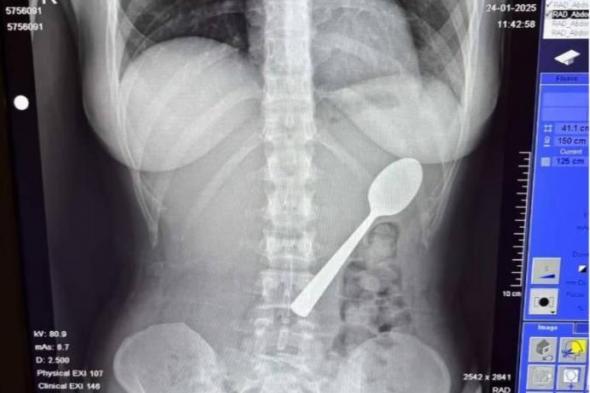

أوقف مدّعي عام النزاهة ومكافحة الفساد الأردني، سائقاً في ...